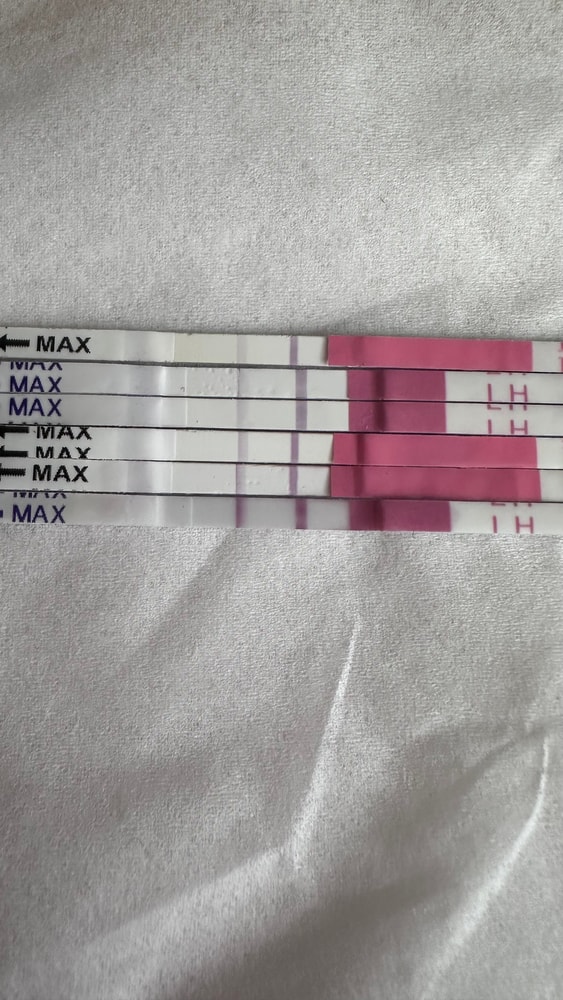

Собрала тесты с цикла в коробку, как всегда😩

Вчера утро:

Сегодня день:

понедельник вечер:

Вторник 7 утра:

Тестик на овуляцию ярчает) я радуюсь как ребенок😂 овуляция с СПКЯ, большая редкость. Последняя была в январе (стимулированная), а предпоследняя в мае 2024 года. 20 д.ц и счаст